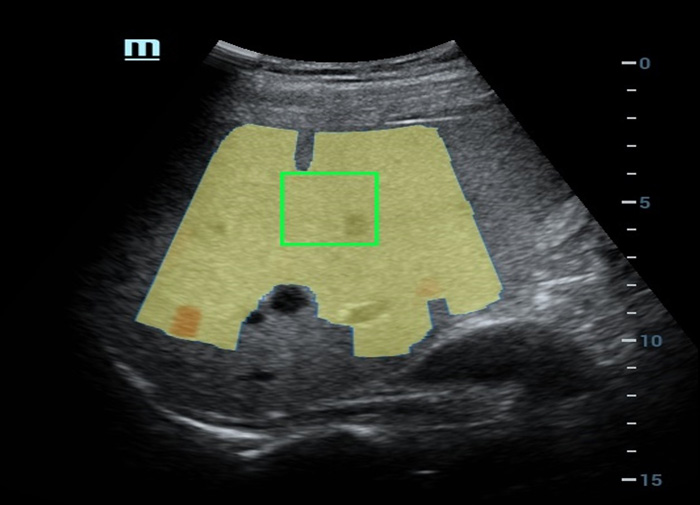

Analisi di laboratorio multiparametriche del fegato grasso

Le analisi di laboratorio multiparametriche del fegato grasso forniscono molteplici strumenti di analisi quantitativa basati su diverse tecnologie acustiche. Consentono di effettuare l'analisi quantitativa della steatosi e migliorano la sensibilitĂ della rilevazione del fegato grasso in fase precoce.